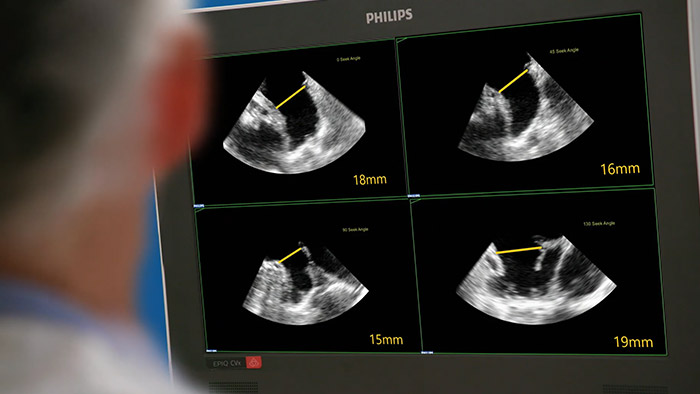

Evalúe la orejuela izquierda de forma rápida, sencilla e intuitiva con la solución para la orejuela izquierda de Philips para EPIQ CVx.